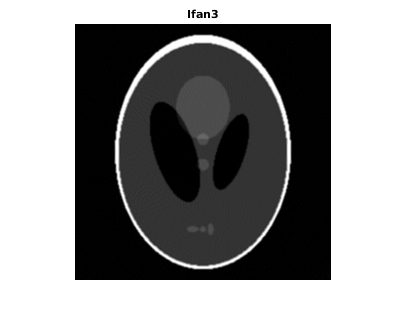

Восстановите изображение из данных о проекции луча вентилятора с помощью ifanbeam . В каждой реконструкции совпадайте с интервалом датчика вентилятора интервалу, используемому, когда данные о проекции были созданы ранее. Пример использует OutputSize параметр, чтобы ограничить выходной размер каждой реконструкции совпадать с размером оригинального изображения P . В выходе отметьте, как качество реконструкции поправляется как количество лучей в увеличениях проекции. Первое изображение, Ifan1 , был создан с помощью 2 интервалов степени лучей; второе изображение, Ifan2 , был создан с помощью 1 интервала степени лучей; третье изображение, Ifan3 , был создан с помощью 0,25 интервалов лучей.

Ifan3 = ifanbeam(F3,D, ... 'FanSensorSpacing',dsensor3,'OutputSize',output_size); figure, imshow(Ifan3) title('Ifan3')